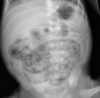

23

Q

A

Large bowel obstruction